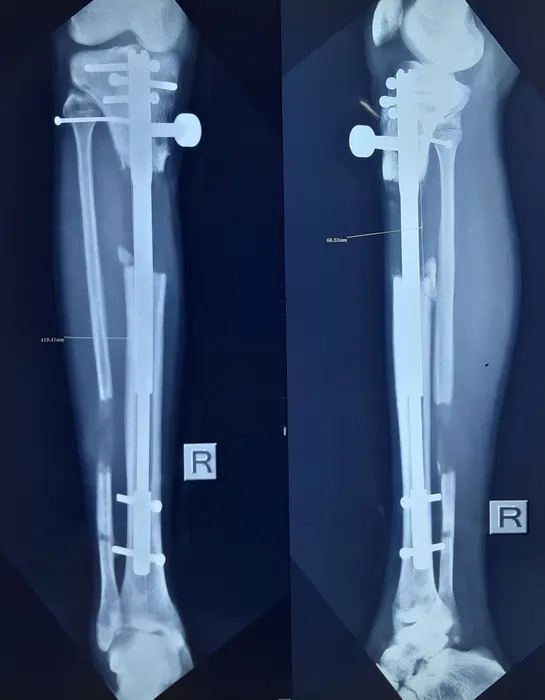

نمونه رادیولوژی افزایش قد ساق با روش MTN (بیمار ۲۰ ساله آقا)

در این تصاویر روند افزایش قد ساق با میله تلسکوپی MTN در یک بیمار ۲۰ ساله را میبینید. در رادیوگرافی قبل از عمل، طول هر دو تیبیا در محدوده ۳۴۳ میلیمتر اندازهگیری شده است. پس از جراحی، میله تلسکوپی MTN داخل هر دو ساق قرار گرفته و استخوان در ناحیه میانی برش داده شده است.

در هفتههای بعد، بیمار روزانه با استفاده از پیچ MTN حدود یک میلیمتر به طول استخوان اضافه کرده است. در رادیوگرافی میانی، فاصله ایجاد شده در محل استئوتومی حدود ۲۰ میلیمتر است و کالوس اولیه در اطراف شکاف دیده میشود. در تصویر بعدی، افزایش طول به حدود ۶٫۸ سانتیمتر رسیده و استخوان جدید تقریباً تمام شکاف را پر کرده است.

در رادیوگرافی نهایی، هر دو ساق هممحور هستند، فضای استئوتومی با استخوان جدید پر شده و طول نهایی ساقها نسبت به قبل از عمل حدود ۶–۷ سانتیمتر بیشتر است. این کیس نشان میدهد که با رعایت برنامه کشش، فیزیوتراپی و کنترل رادیولوژیک منظم، میتوان افزایش قد قابلتوجهی را با حفظ هممحوری اندام و پایداری ایمپلنت بهدست آورد.

(نتایج هر بیمار منحصر بهفرد است و میزان افزایش قد و سرعت جوش خوردن استخوان میتواند متفاوت باشد.)

در این بیمار، هممحوری مکانیکی ساقها حفظ شده و کالوس متراکم در ناحیه استئوتومی دیده میشود.